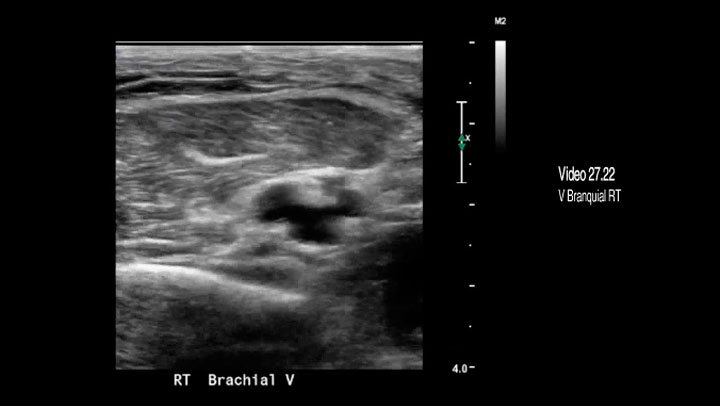

Video 27.22 Trombo no oclusivo en una vena braquial en las venas braquiales emparejadas